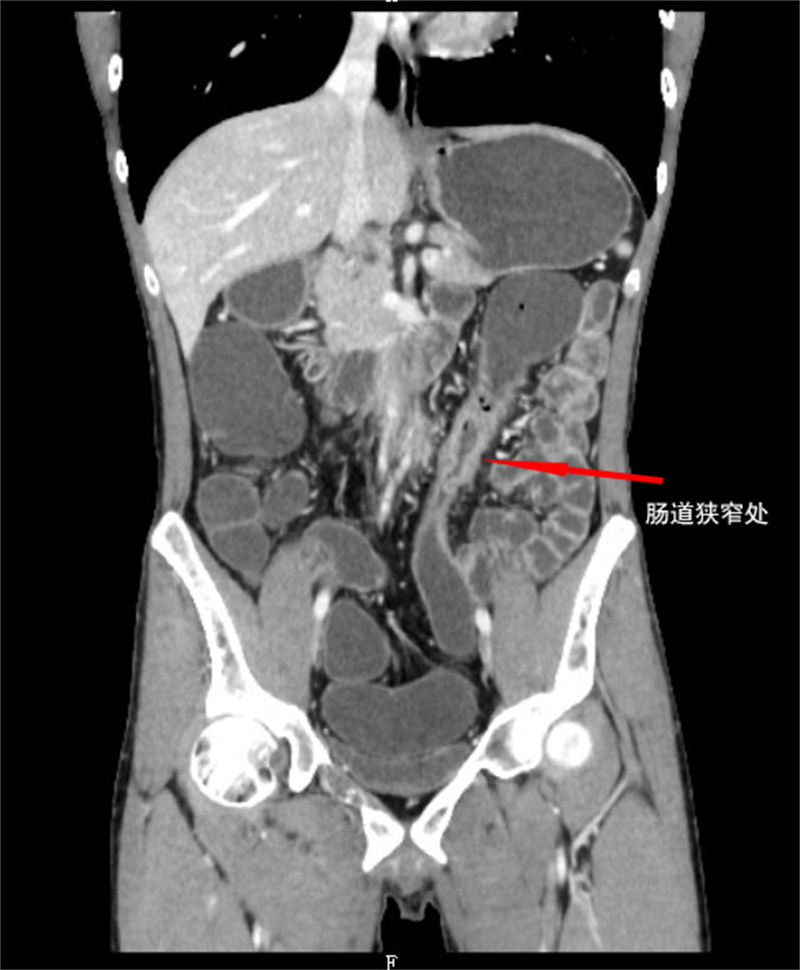

影像学中可以看到结肠狭窄、肠瘘